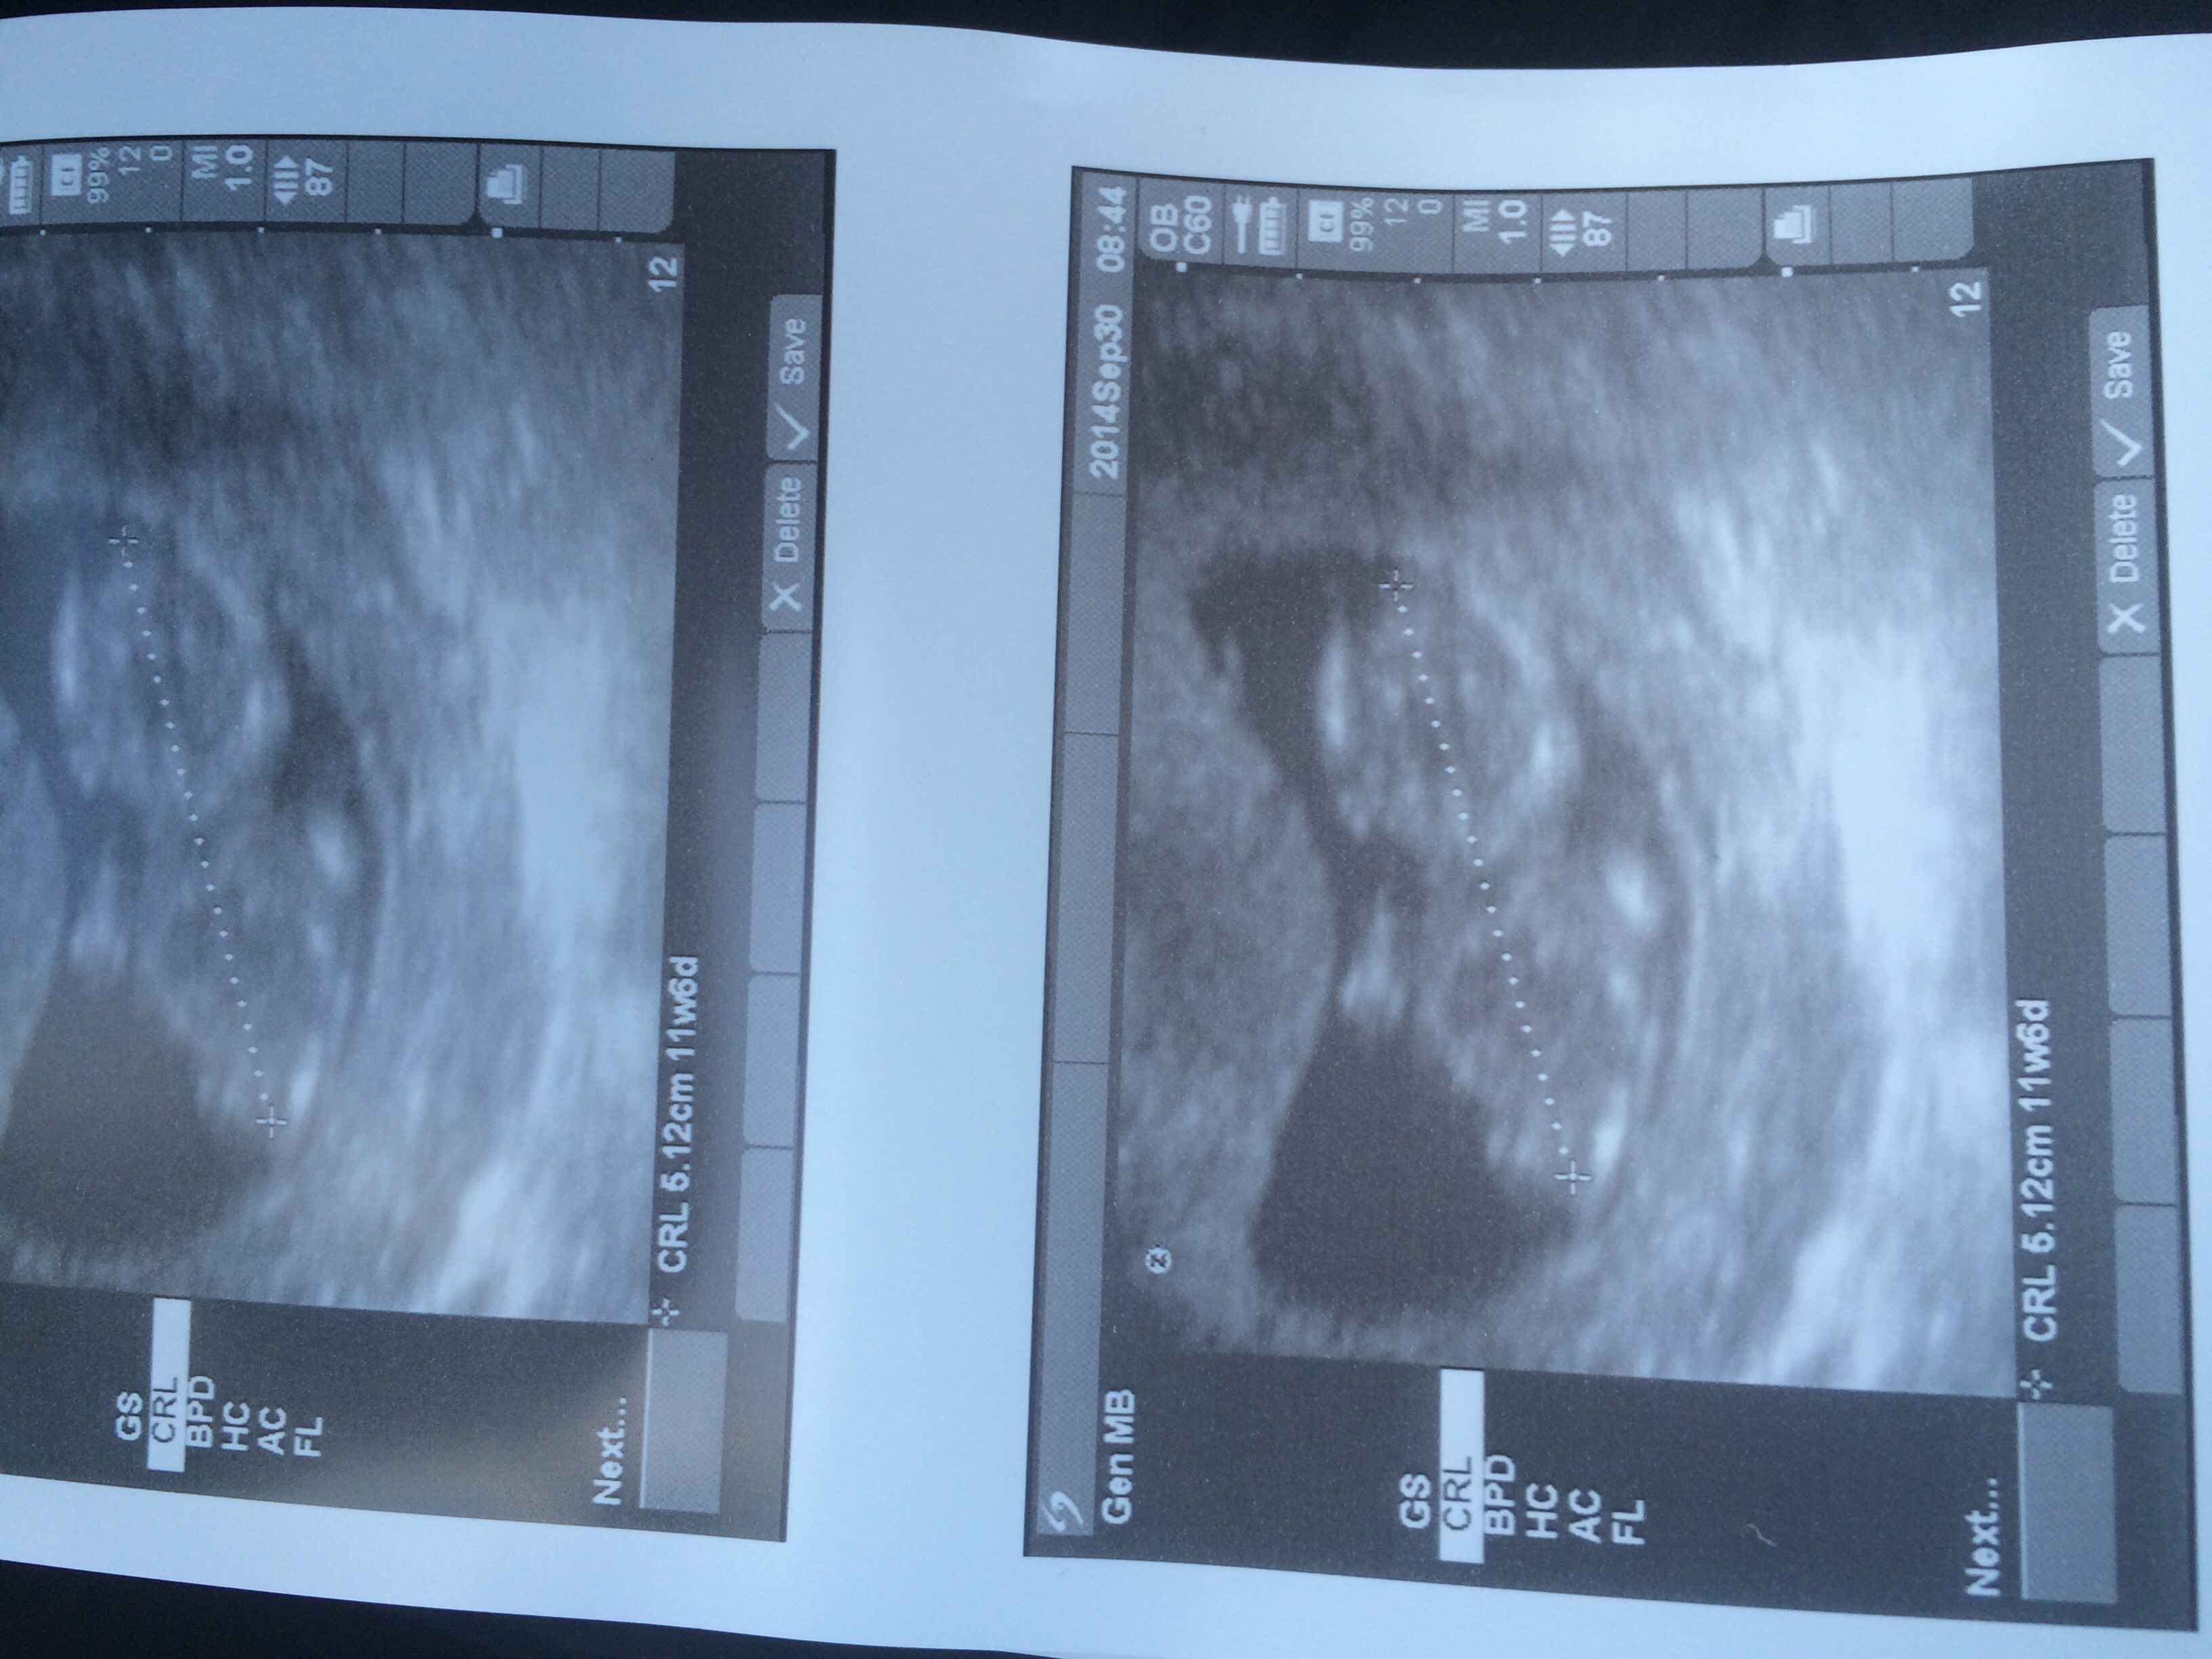

Finally had my first appointment yesterday! Our sweet little babe was measuring a few days ahead (actually right in line with LMP whereas I had been estimating based on later O). New EDD is 4/22 which makes me 11 weeks today! We heard a perfect heartbeat of 162. :x